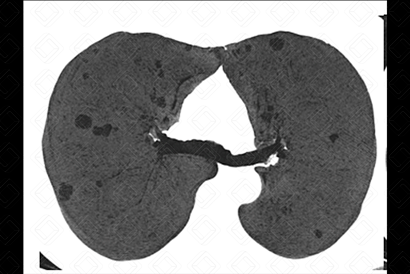

[cms-watermark] Descrição das figuras: Tomografia computadorizada com projeção em intensidade mínima - MnIP (mulher, 64 anos, portadora de síndrome de Sjögren). Múltiplos cistos, menores que 10 mm, de paredes finas e de distribuição bilateral.

• Tomografia computadorizada do tórax: A pneumonia intersticial linfocítica caracteriza-se pela presença de múltiplos cistos com distribuição randômica, isto é, aleatória, em adjacência a vasos sanguíneos. Nódulos pulmonares, usualmente, são achados encontrados em associação, auxiliando no diagnóstico diferencial com outras doenças císticas (figuras acima).